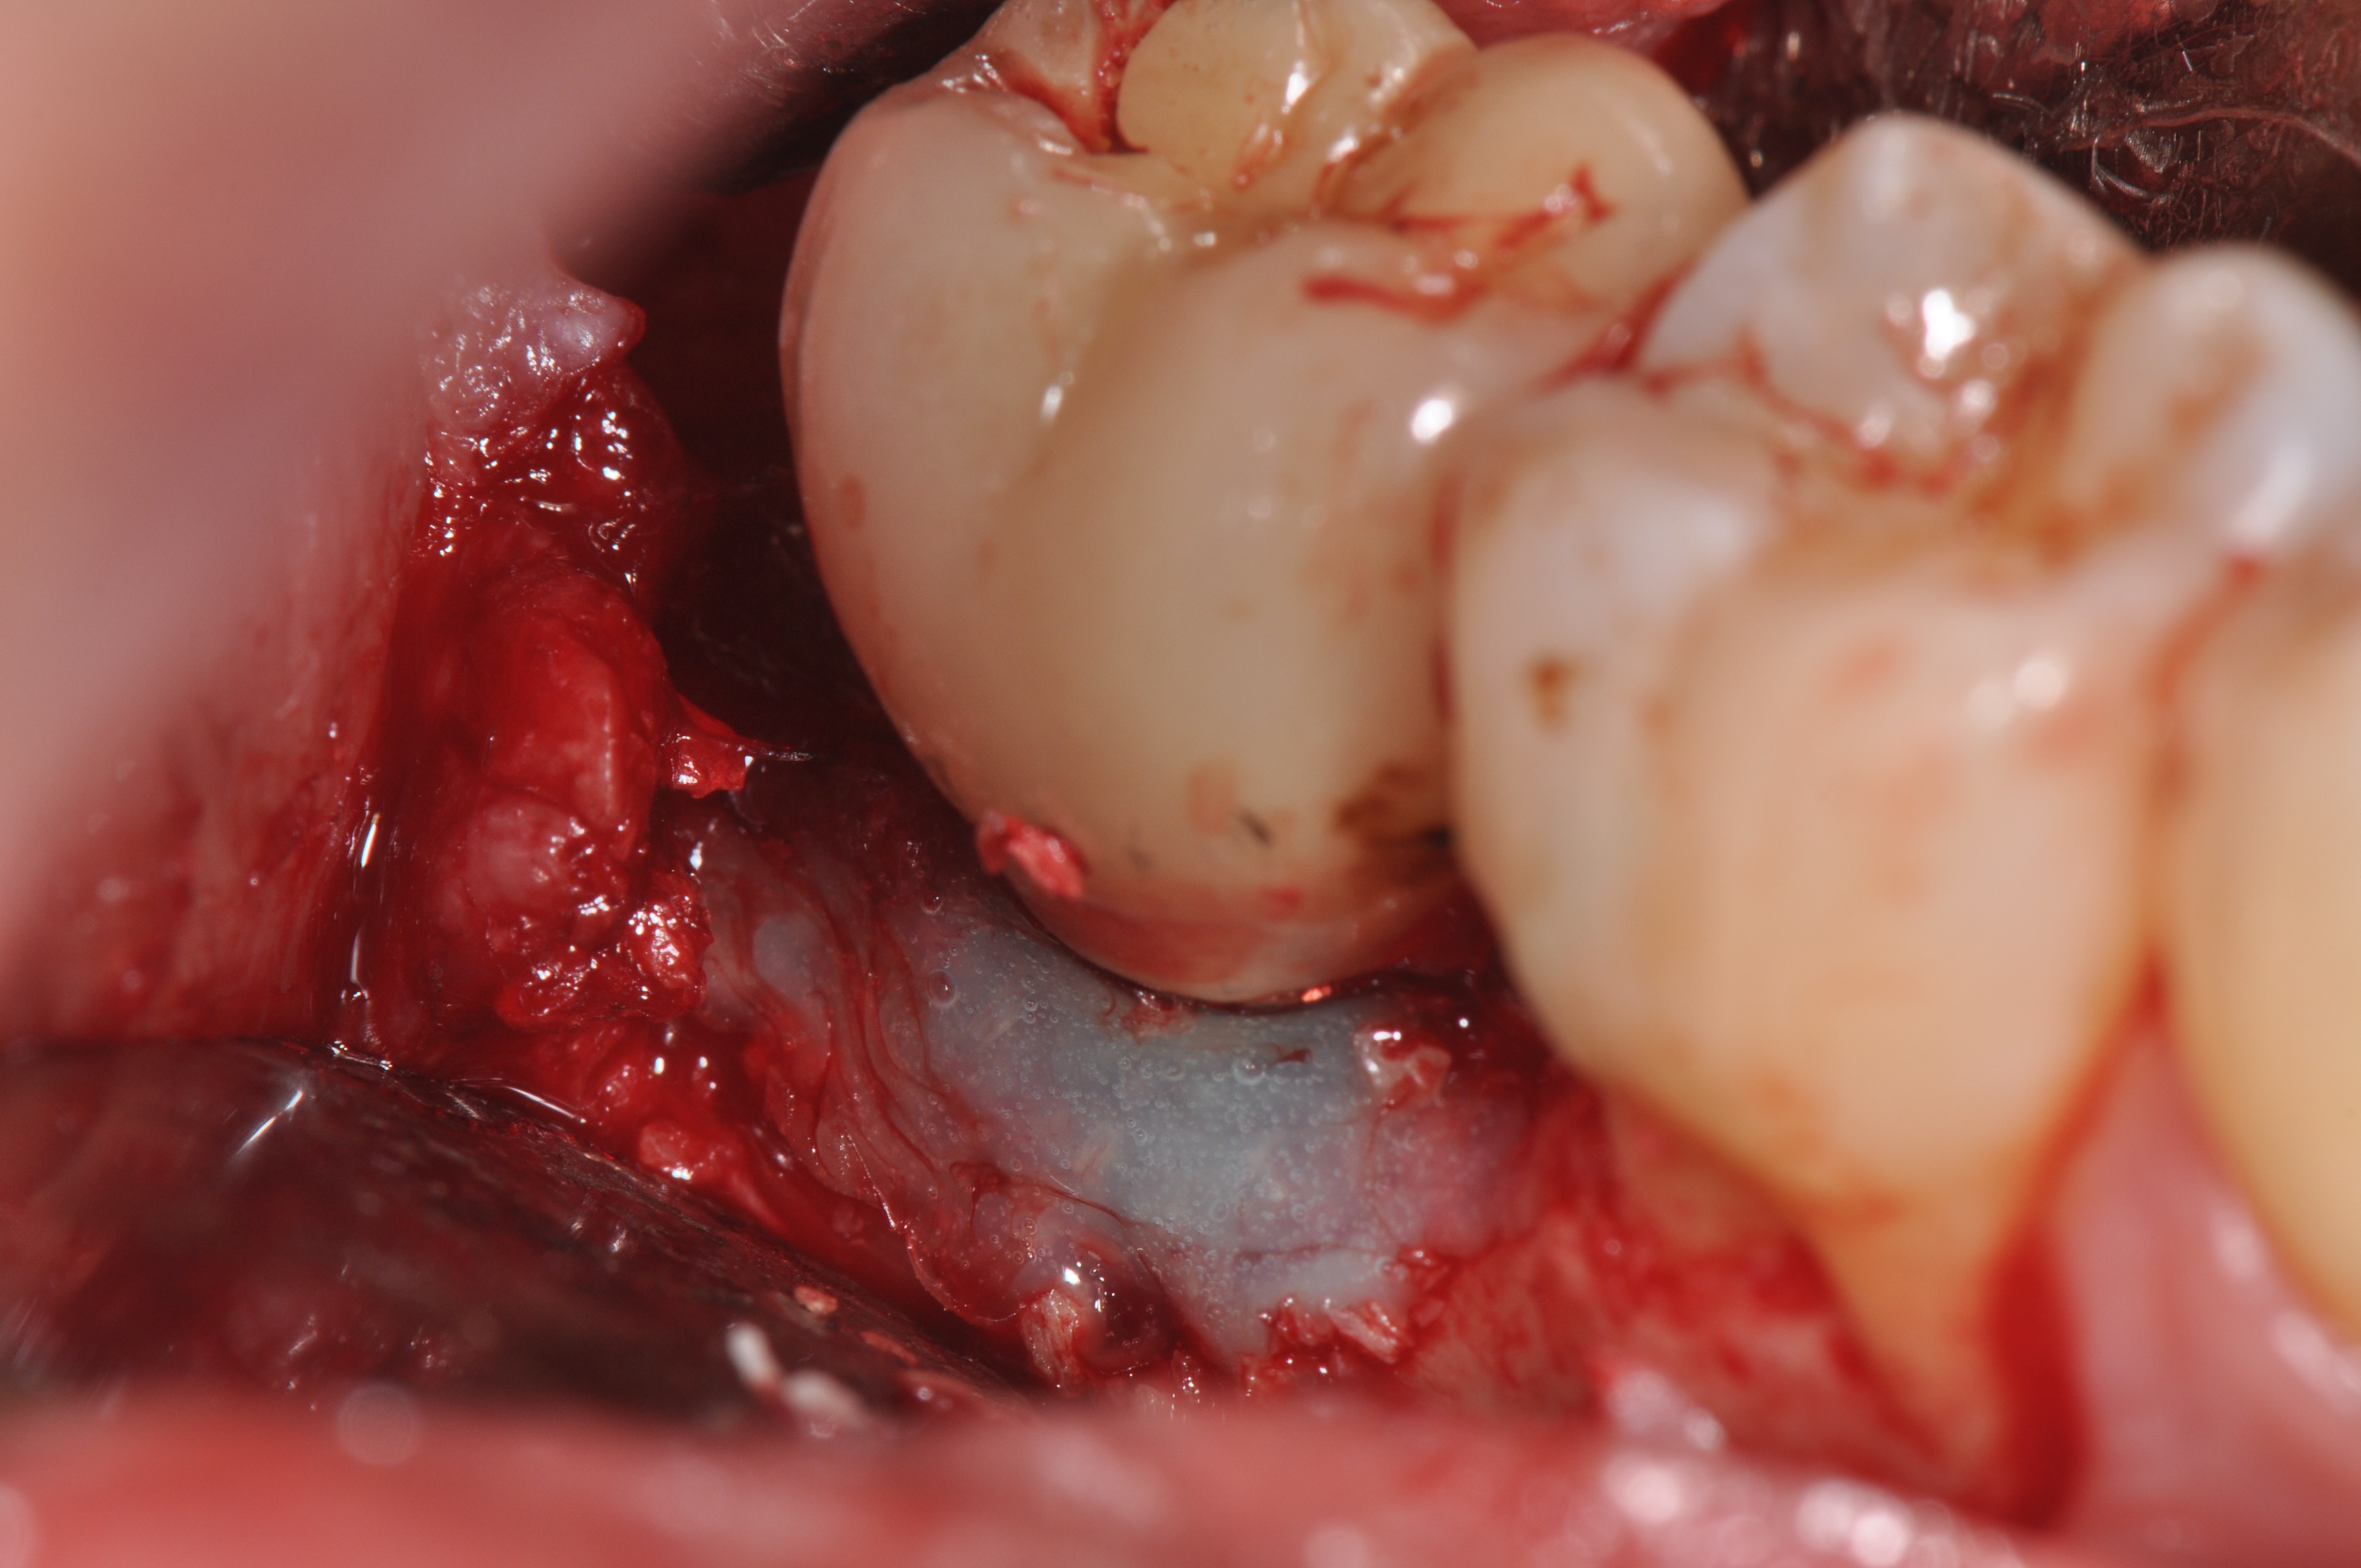

Clinical exposure of a circumferential lesion that demonstrates 3 mm of bone loss. No cement was present, suggesting that the lesion was of bacterial origin. Surface decontamination included citric acid.

Figure 2